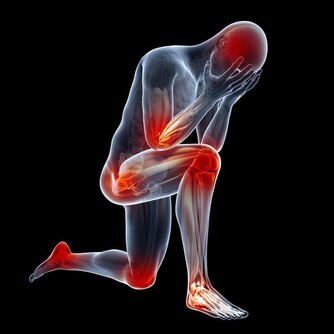

* 低體溫對身體的影響

既然高體溫對身體有如此種種好處,與它對立的低體溫自然也會對身體產生一些影響,這些影響則多半是負面的。

容易產生輕度疾病

具有調節體溫機能的腦下視丘,同時也是控制自律神經及激素的中樞。因此,低體溫會影響自律神經功能以及激素平衡,進而引起肩膀僵硬、頭痛、暈眩、手腳冰冷等症狀。另外,體溫偏低與月經不調、經前症候群等婦科病也有關聯。

內臟功能低下

體溫降低,包括消化酵素在內的有助於內臟活動的各種酵素機能都相應降低。體溫每下降1℃,酵素的活力便會降低50%,因此人容易感到疲倦,各種不舒服的症狀,如便秘、胃脹氣、尿量減少等,都會頻頻出現。

免疫力降低

侵入人體的細菌及病毒要由體內的白血球來對抗,但每當體溫降低1℃,白血球所提供的免疫力便會減少37%,因此體溫較低的人,在季節交換時比較容易感冒。

血液循環變差

低體溫的人,手腳的末梢血管會緊縮,血液自然不易流通。更會因心臟輸送血液的力量減弱,使全身的血液循環變差。另外,也可能因自律神經發揮的功能降低,導致血管收縮能力受到影響,血液的流通受到阻礙。